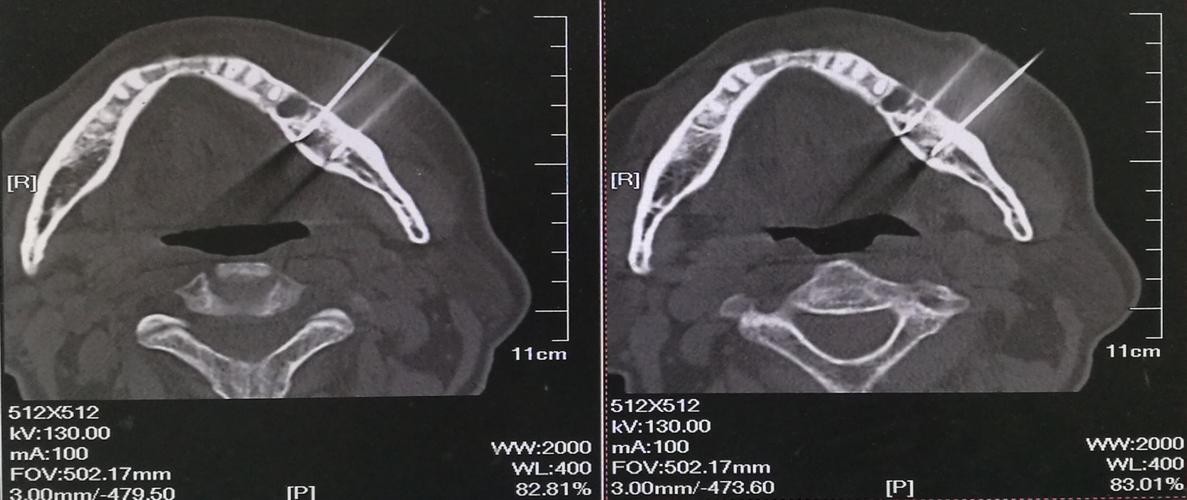

1.好发于下颌骨,特别是下颌磨牙区,于发病部位出现实质性肿块,生长迅速,扪诊无乒乓感,可有压痛。